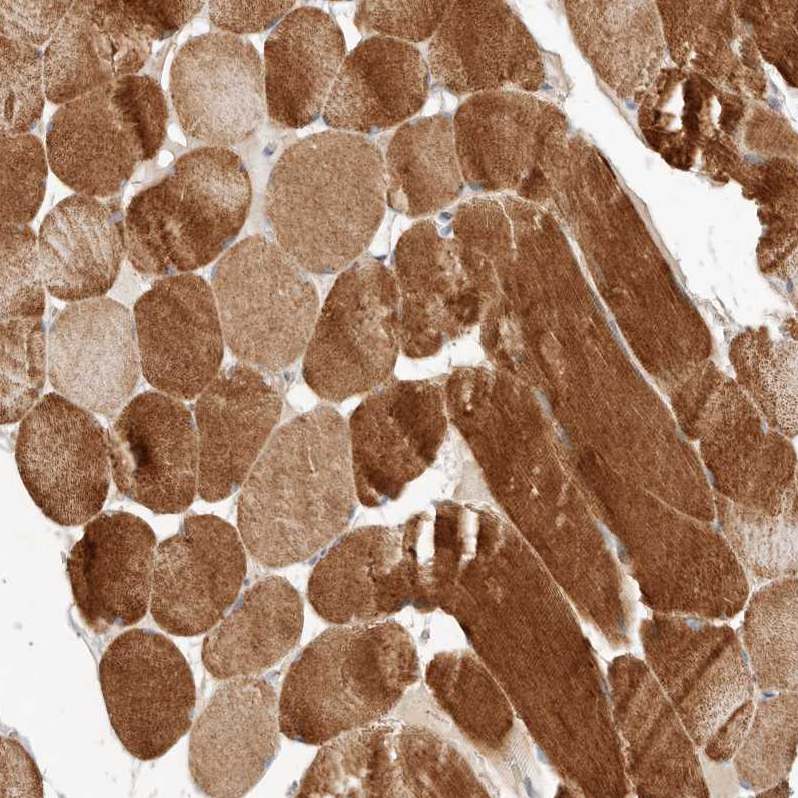

Immunohistochemical staining of human liver shows weak granular cytoplasmic positivity in hepatocytes.